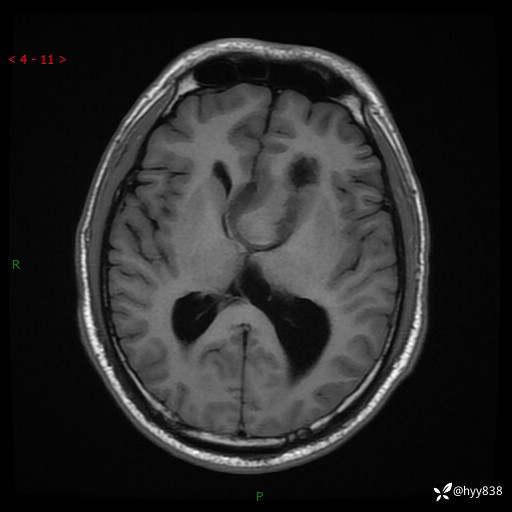

颅脑MRI平扫+增强